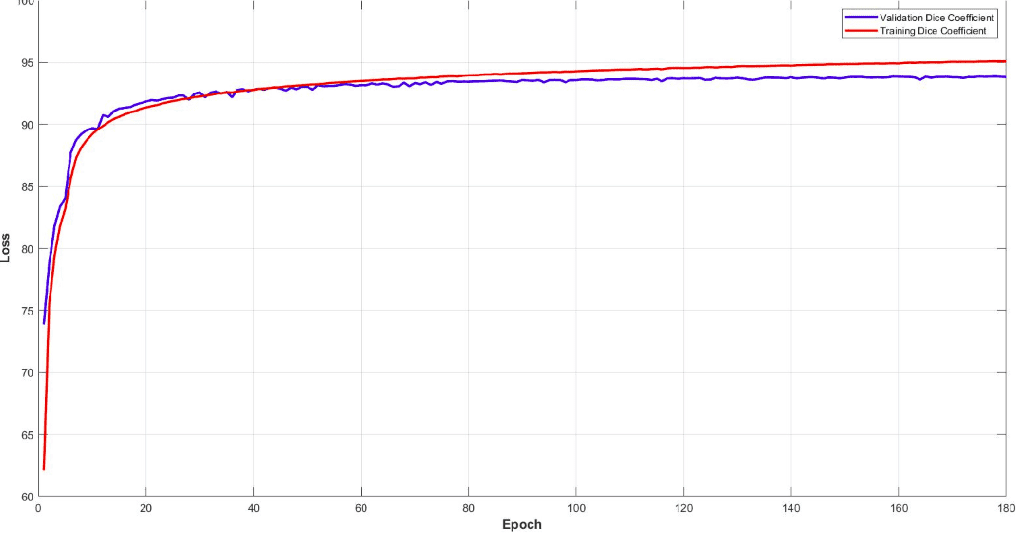

下面你可以看到模型的训练和验证骰子损失曲线。监控您的模型性能并调整参数以获得如此平滑的训练曲线非常重要。很容易理解这个模型的效率。

该模型在子卷的验证集中达到了大约 93% 的骰子系数分数。最后但同样重要的是,让我们看看验证集中 3D-Unet 的一些可视化预测。尽管预测是 3D 体积,但我们在这里只展示一个代表性切片。通过获取 MRI 的多个子体积,可以将它们组合起来形成完整的 3D MRI 分割。请注意,我们使用子卷采样的事实是数据增强。

最近我们还使用 Pytorch 添加了Tensorboard可视化。这个惊人的功能可以让你保持清醒,让你跟踪模型的训练过程。您可以在下面看到一个保留训练统计数据、骰子系数和损失以及每类分数以了解模型行为的示例。

很明显,不同的组织具有不同的精度,即使从训练开始也是如此。例如,查看验证集中从高值开始的空气体素,因为它是不平衡数据集的最主要类别。另一方面,灰质从最低值开始,因为它最难区分且训练实例较少。